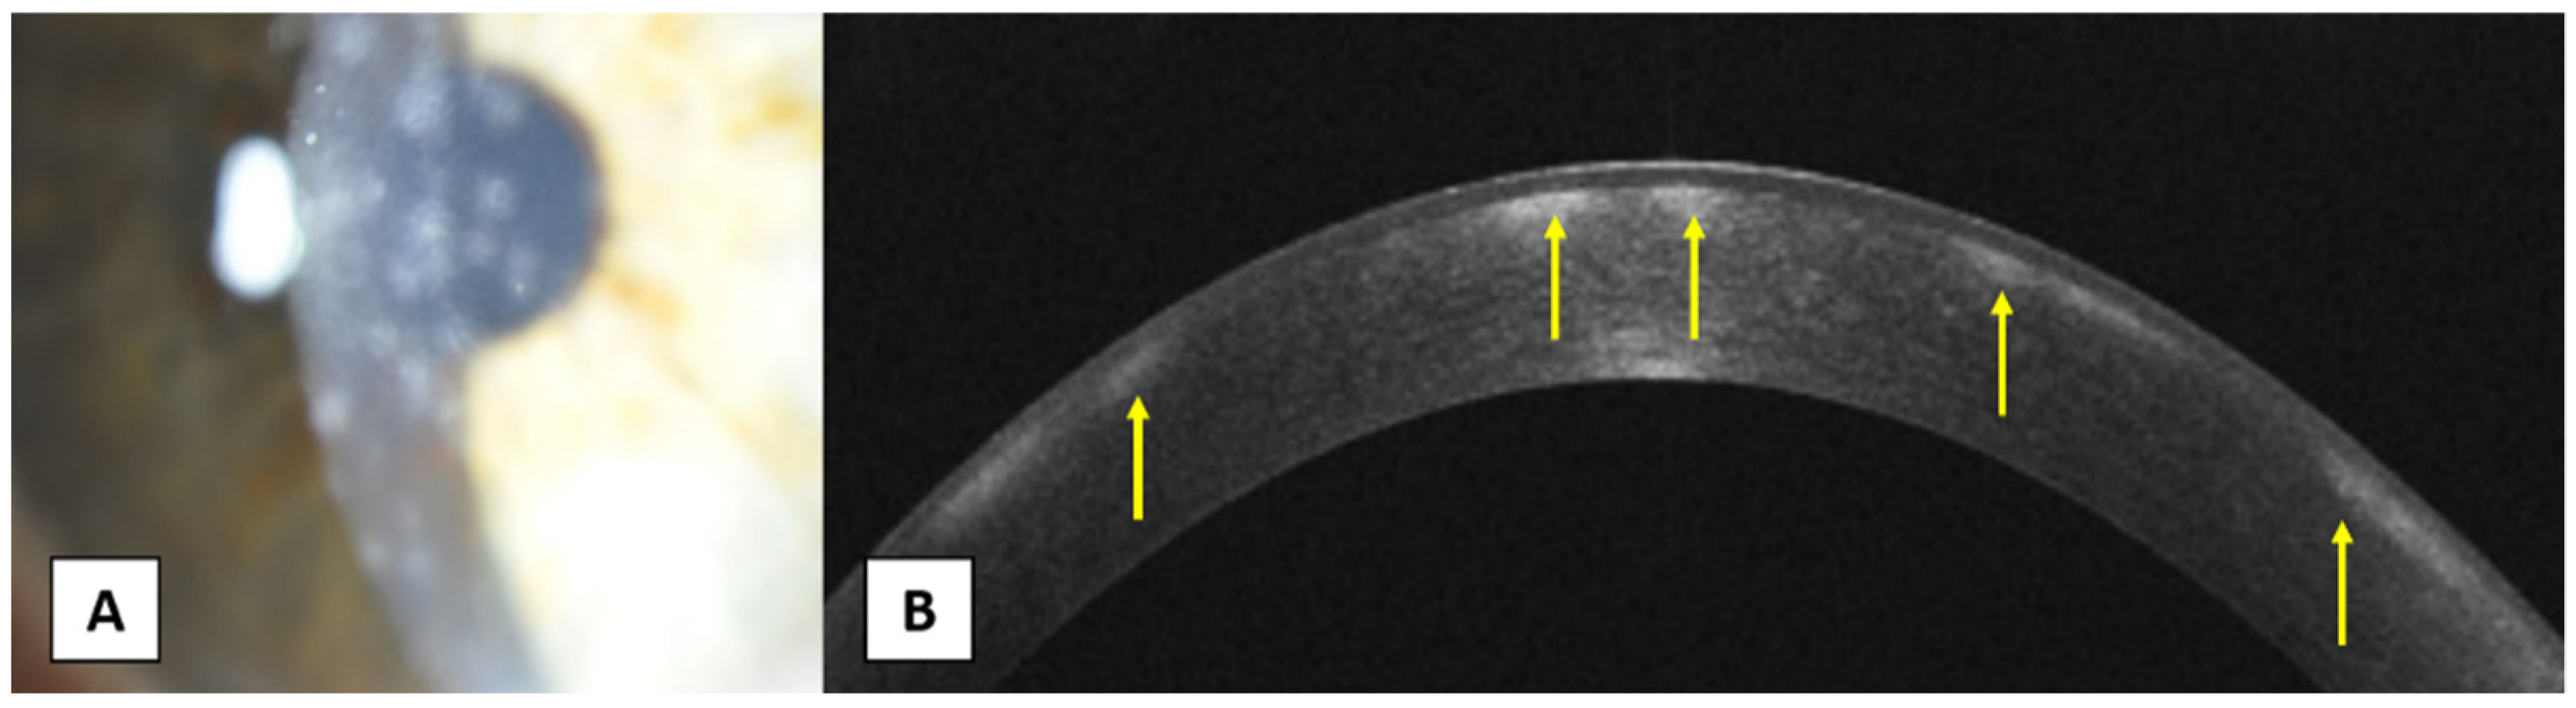

- Sridhar, M.S.; Shaik, B. Anterior segment optical coherence tomography of microsporidial keratoconjunctivitis. Indian J. Ophthalmol. 2018, 66, 691–692. [Google Scholar] [CrossRef] [PubMed]

- Thanathanee, O.; Laohapitakvorn, S.; Anutarapongpan, O.; Suwan-Apichon, O.; Bhoomibunchoo, C. Anterior Segment Optical Coherence Tomography Images in Microsporidial Keratoconjunctivitis. Cornea 2019, 38, 943–947. [Google Scholar] [CrossRef]